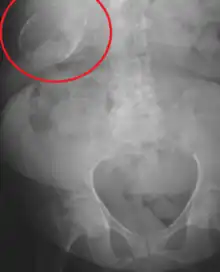

Porcelain gallbladder on X-ray

Porcelain gallbladder is a calcification of the gallbladder believed to be brought on by excessive gallstones, although the exact cause is not clear. As with gallstone disease in general, this condition occurs mostly in overweight female patients of middle age. It is a morphological variant of chronic cholecystitis. Inflammatory scarring of the wall, combined with dystrophic calcification within the wall transforms the gallbladder into a porcelain-like vessel. Removal of the gallbladder (cholecystectomy) is the recommended treatment.

Abdominal radiography (X-ray), abdominal ultrasound or CT scan.